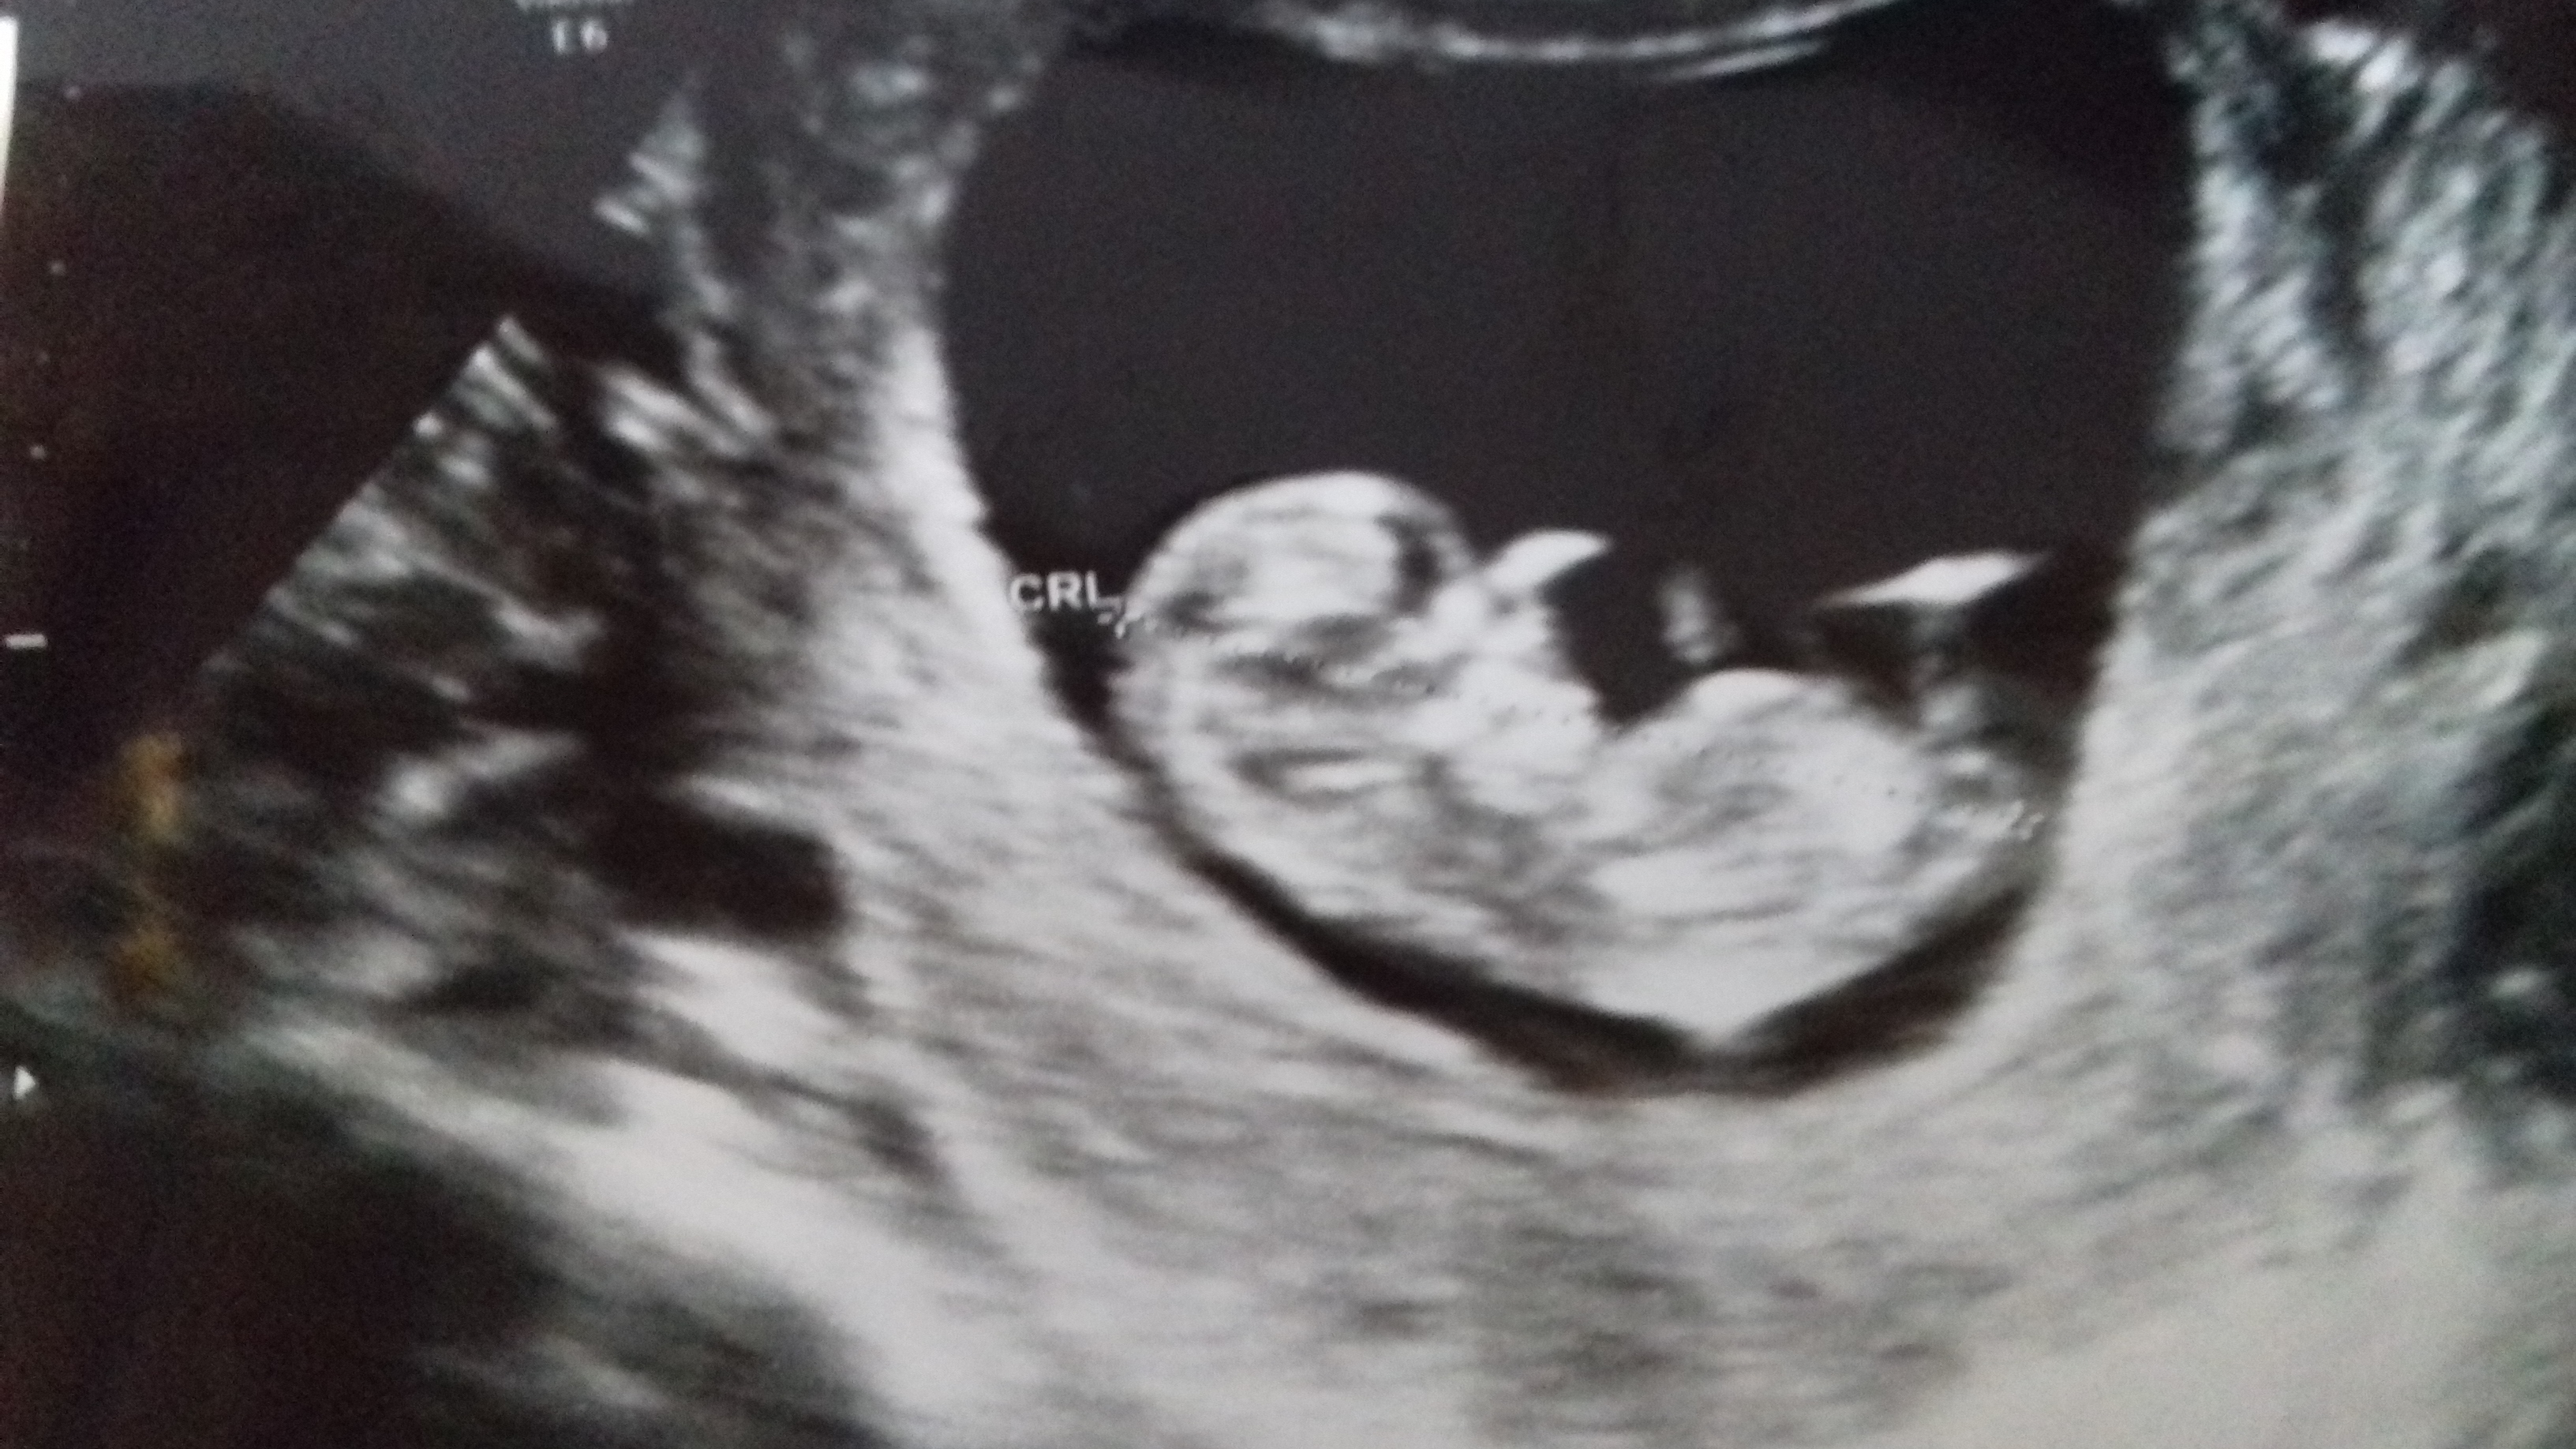

The first pic looks like a boy to me and the second pic looks girlie.

Leaning towards girl from second pic - I'm still learning how to 'read' nubs so please dont put any stock in my guess :)

Last pics look more girly but I think boy, hope I'm wrong. First one looks like boy nub and second one would look girly if no stacking (but could very well be baby's leg in the way). Even the last pic has a line under nub which might suggest boy. But really hope it is your baby girl!